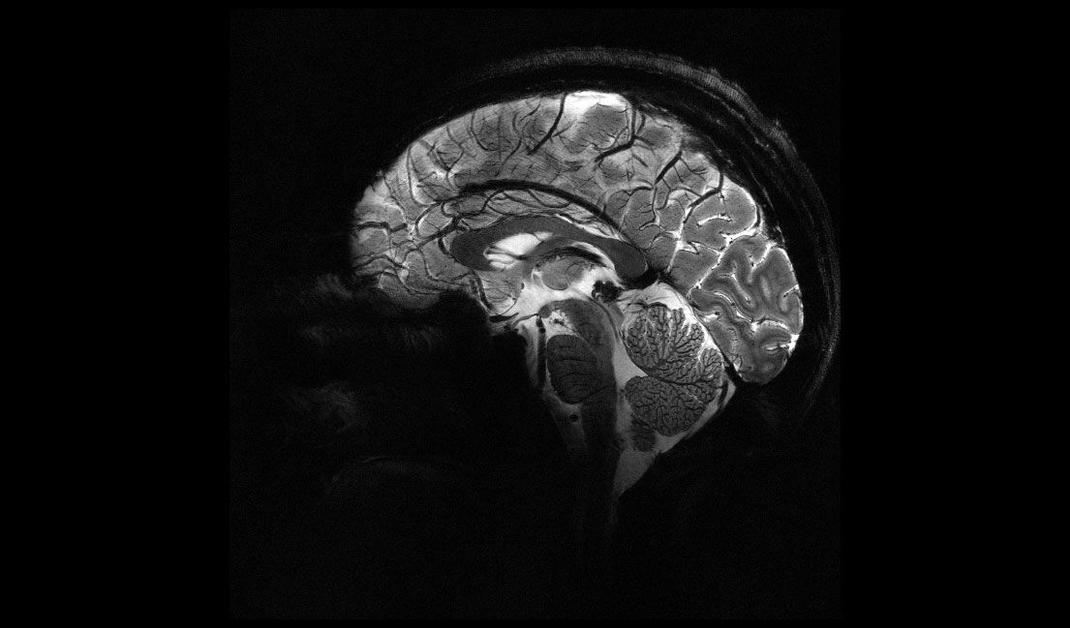

L'IRM « le plus puissant du monde » dévoile ses premières images de notre cerveau

Le Commissariat à l'énergie atomique et aux énergies alternatives a dévoilé ce mardi 2 avril les premières images de l'IRM Iseult, le plus puissant du monde. Il doit aider à mieux comprendre le fonctionnement du cerveau.